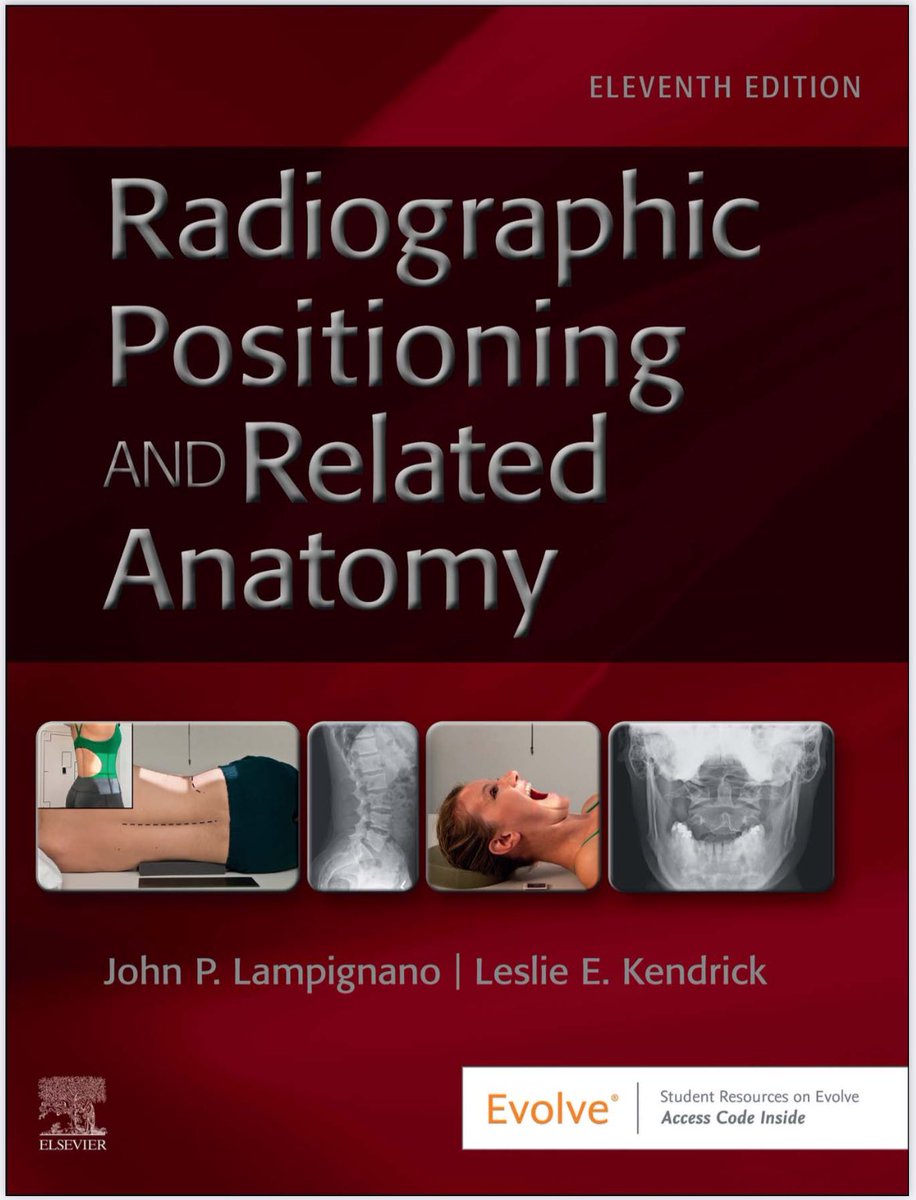

مرجع مميز للمهتمين في الأشعة العامة والتصوير الطبي

يفهمك الأوضاع التصويرة + وعلم الأمراض بطريقة واضحة وسلسلة بالإضافة إلى كتيب التدريب شامل لجميع الاسئلة الشائعة في مجال الأشعة

#radiology #radiography #xray #radiographer #radtech #srtle

من الاسئلة الاكثر أهمية في تصوير الركبة بالأشعة السينية فلنتشارك في الحل

SELF-TEST:

POSITIONING OF THE LOWER LIMB

Answer the following questions by selecting the best choice.

Reference (Merrill’s Atlas 12 edition)